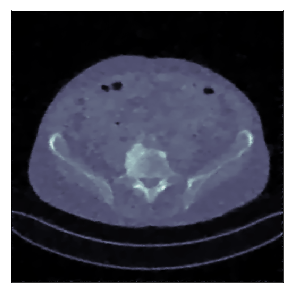

We consider the variational reconstruction framework for inverse problems and propose to learn a data-adaptive input-convex neural network (ICNN) as the regularization functional. The ICNN-based convex regularizer is trained adversarially to discern ground-truth images from unregularized reconstructions. Convexity of the regularizer is desirable since (i) one can establish analytical convergence guarantees for the corresponding variational reconstruction problem and (ii) devise efficient and provable algorithms for reconstruction. In particular, we show that the optimal solution to the variational problem converges to the ground-truth if the penalty parameter decays sub-linearly with respect to the norm of the noise. Further, we prove the existence of a sub-gradient-based algorithm that leads to a monotonically decreasing error in the parameter space with iterations. To demonstrate the performance of our approach for solving inverse problems, we consider the tasks of deblurring natural images and reconstructing images in computed tomography (CT), and show that the proposed convex regularizer is at least competitive with and sometimes superior to state-of-the-art data-driven techniques for inverse problems.